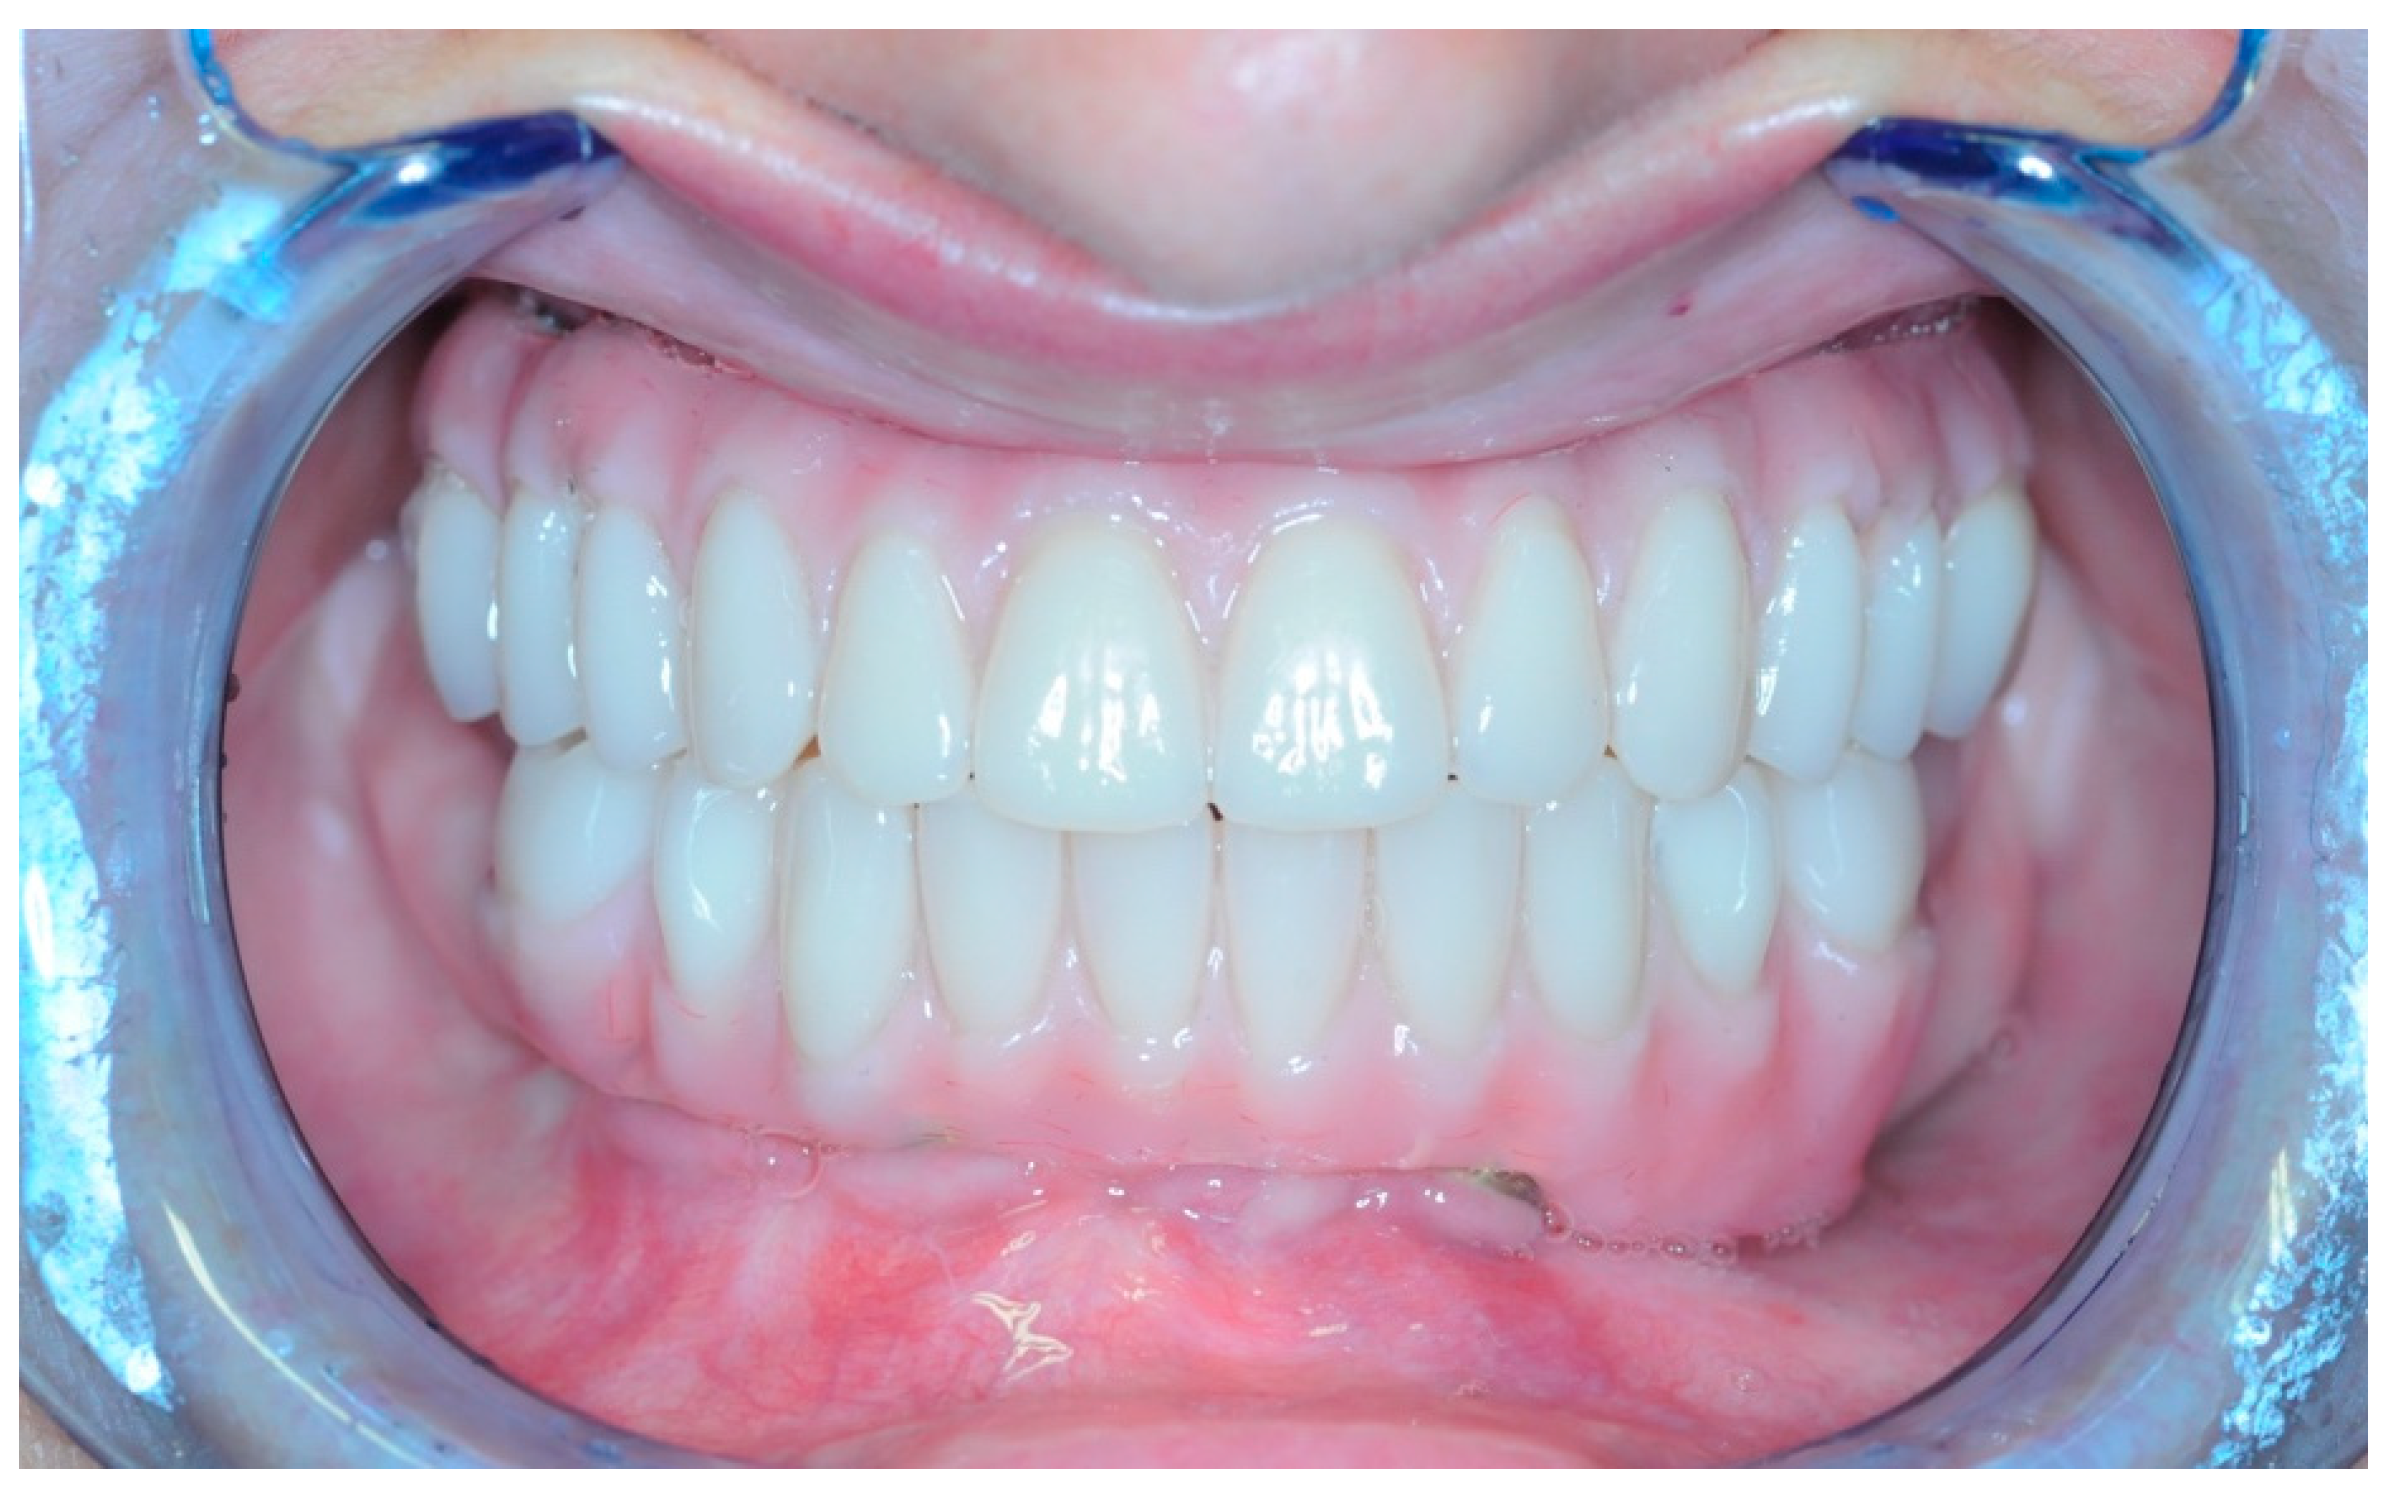

2.5. Final Prosthesis

3. Results

3.5. Function and Aesthetics